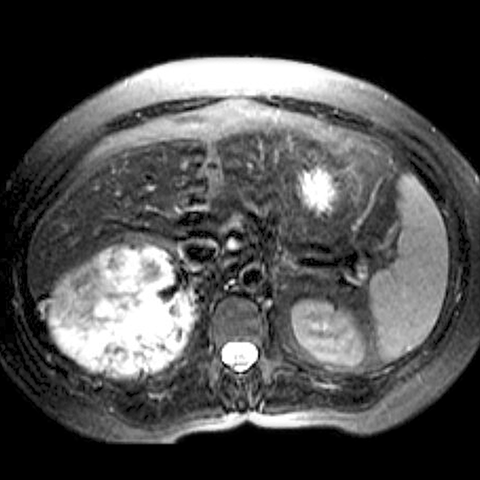

42-year-old-male presents with episodic headache, diaphoresis, and tachycardia. [3 of 3]